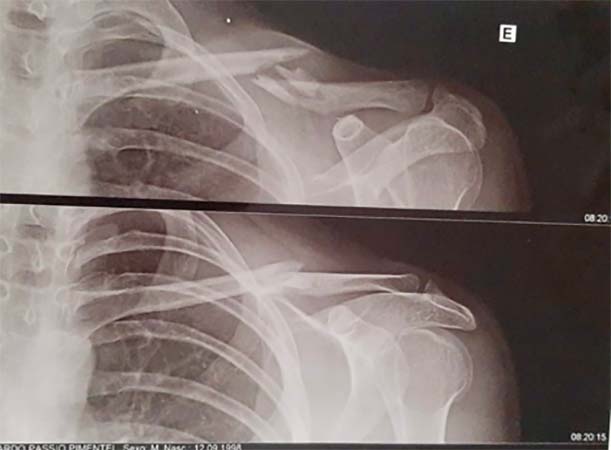

LUXAÇÃO ACROMIOCLAVICULAR

A luxação acromioclavicular consiste na perda de contato entre a clavícula e o acromio ( parte do osso da escapula). Isto ocorre em decorrência a um trauma na parte lateral do ombro. Com a luxação temos a impressão que a clavícula ascendeu. Além da deformidade o paciente apresenta uma dor intensa na região lateral do ombro. Para o diagnóstico utilizamos a radiografia. E com ela avaliamos o grau da luxação da clavícula. Para casos mais simples apenas uma tipoia por três semanas é utilizada no tratamento. Para os casos mais graves a cirurgia é indicada como o tratamento de escolha.